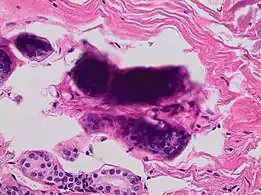

A crush artifact is an artificial elongation and distortion seen in histopathology and cytopathology studies, presumably because of iatrogenic compression of tissues. Distortion can be caused by the slightest compression of tissue and can provide difficulties in diagnosis.[2][3] It may cause chromatin to be squeezed out of nuclei.[4] Inflammatory and tumor cells are most susceptible to crush artifacts.[4]

6. Image by Mikael Häggström, MD. Source for findings: Caroline I.M. Underwood, M.D., Carolyn Glass, M.D., Ph.D. "Lung - Small cell carcinoma". Pathology Outlines.{{cite web}}: CS1 maint: multiple names: authors list (link) Last author update: 20 September 2022